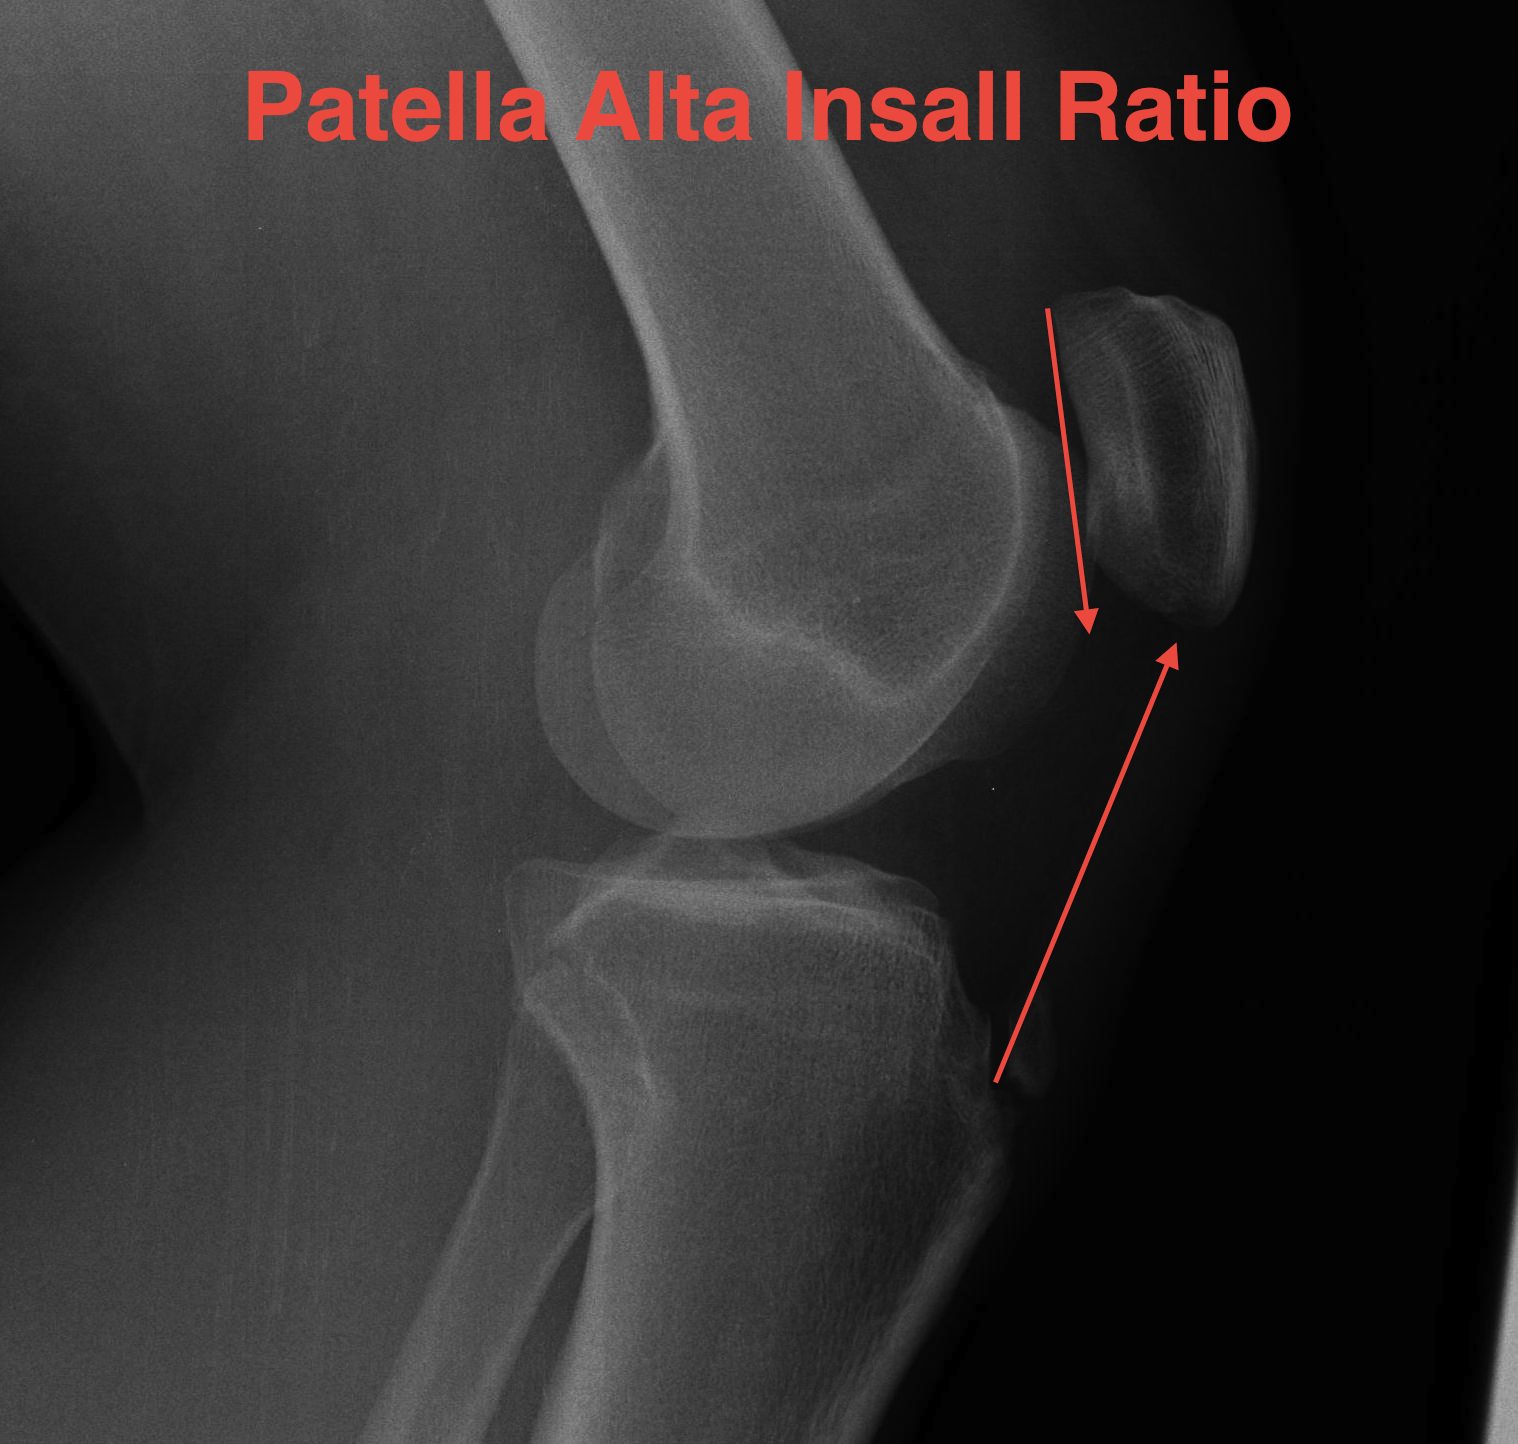

C. Insall ratio

- less accurate, probably because more difficult to measure

- ratios also difficult to remember and calculate

- length of patella tendon v length patella

- patella alta LT : LP 1.2

- patella baja LT : LP <1